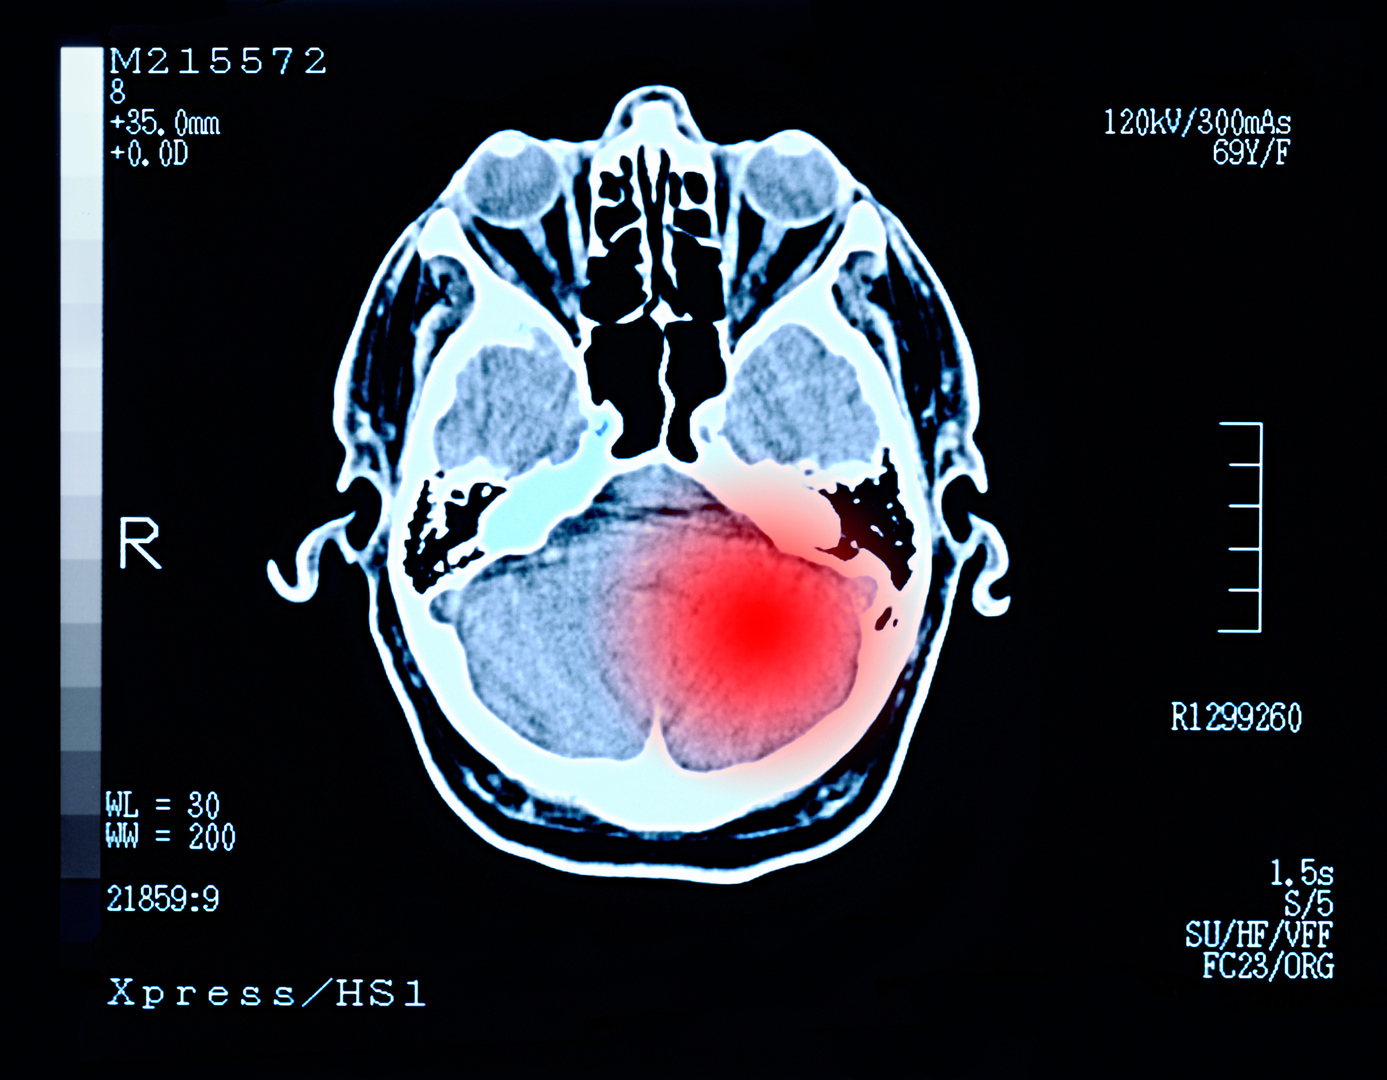

- تحذير طبي من مرض شائع يزيد خطر الإصابة بنوعين من السرطان